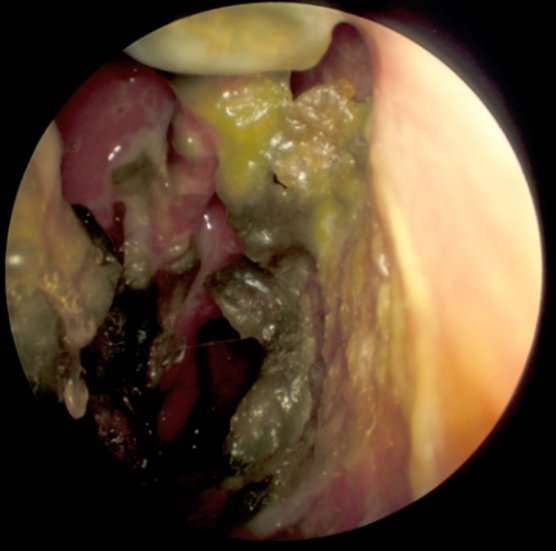

▼这种病症,是有「食肉菌」会将她的皮肤软组织给慢慢吞噬。在照过鼻镜后,她被告知「脸部里是空的」。

▼后来当她打喷嚏的时候,不只鼻孔流出了一大堆血,连鼻中膈也掉了出来。